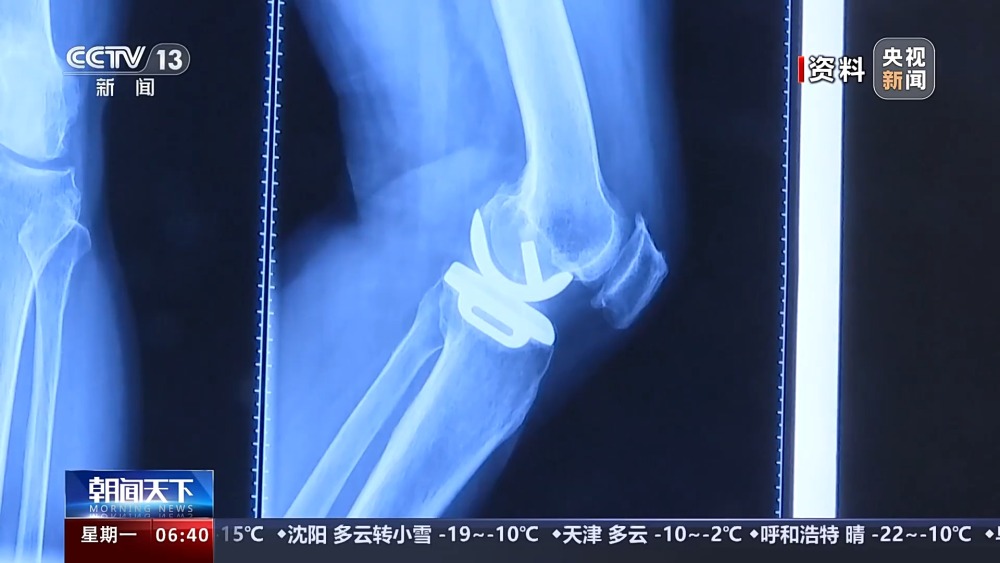

目前,我國有超過1億人患有骨關(guān)節(jié)炎,65歲以上人群中,骨關(guān)節(jié)炎發(fā)病率接近50%。以前,嚴(yán)重骨關(guān)節(jié)炎患者主要通過膝關(guān)節(jié)置換手術(shù)來維持行走等基本功能。膝關(guān)節(jié)置換手術(shù)存在術(shù)后關(guān)節(jié)僵硬、長期疼痛等問題。保膝治療包括藥物、理療等保守治療,以及手術(shù)治療。

保膝手術(shù)主要包括截骨術(shù)和單髁置換術(shù),其中截骨術(shù)在解決患者疼痛癥狀的同時(shí),阻止下肢異常應(yīng)力對(duì)膝關(guān)節(jié)的進(jìn)一步損傷,膝關(guān)節(jié)內(nèi)所有軟骨韌帶、半月板都得到了保留。內(nèi)側(cè)單髁置換術(shù),使膝關(guān)節(jié)外側(cè)健康的軟骨和半月板得到了保留,膝關(guān)節(jié)內(nèi)外側(cè)的韌帶維持原有狀態(tài),患者康復(fù)后,擁有正常的膝關(guān)節(jié)功能。